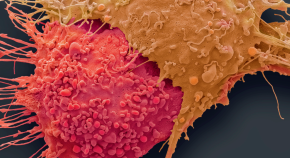

Welcome to Nature Research Tech, our home for life-science technology coverage from across Nature Research.

Here, we spotlight the technology behind the science, allowing the materials, methods, and instrumentation that make science possible to take center stage. Our goal: to provide current and need-to-know information that scientists can implement in their own labs.